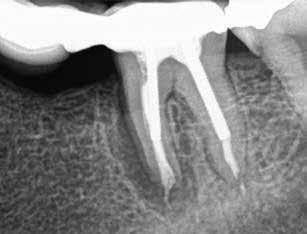

1. a-n. ábrák: Preoperatív CBCT-felvétel a bal alsó 6-os (3.6) fogról. Az axialis (a), coronalis (b) és sagittalis (c) nézeteken a mezialis és distalis gyökerek apicalis harmada körül sugáráteresztő zóna és ép buccalis corticalis csont látható. Egy olyan sablont terveztünk, amely jelezte a csontablak határait az apicalis terület pontos elérése érdekében (d). A mikrosebészeti bevatkozás során a sablont a helyére illesztettük (e), a csontablak határait megjelöltük (f) egy Piezotome CUBE LED kézi-darabba fogott fűrésszel, majd kivágtuk és eltávolítottuk (g és h) az apicalis területhez történő hozzáférés, illetve a mezialis és distalis gyökerek rezekciójának, retrográd preparációjának és retrográd gyökértömésének elvégzése érdekében (i). Végezetül a csontablakot visszaillesztettük és kollagén szivaccsal stabilizáltuk (j). A műtét után közvetlenül készített röntgenfelvétel a 3.6-os fogról (k). A kétéves kontroll során készített CBCT-felvétel: axialis (l), coronalis (m) és sagittalis (n) nézetek.

1a 1b 1c 1d

1e 1g 1h 1i 1j 1k 1f

1l 1m 1n